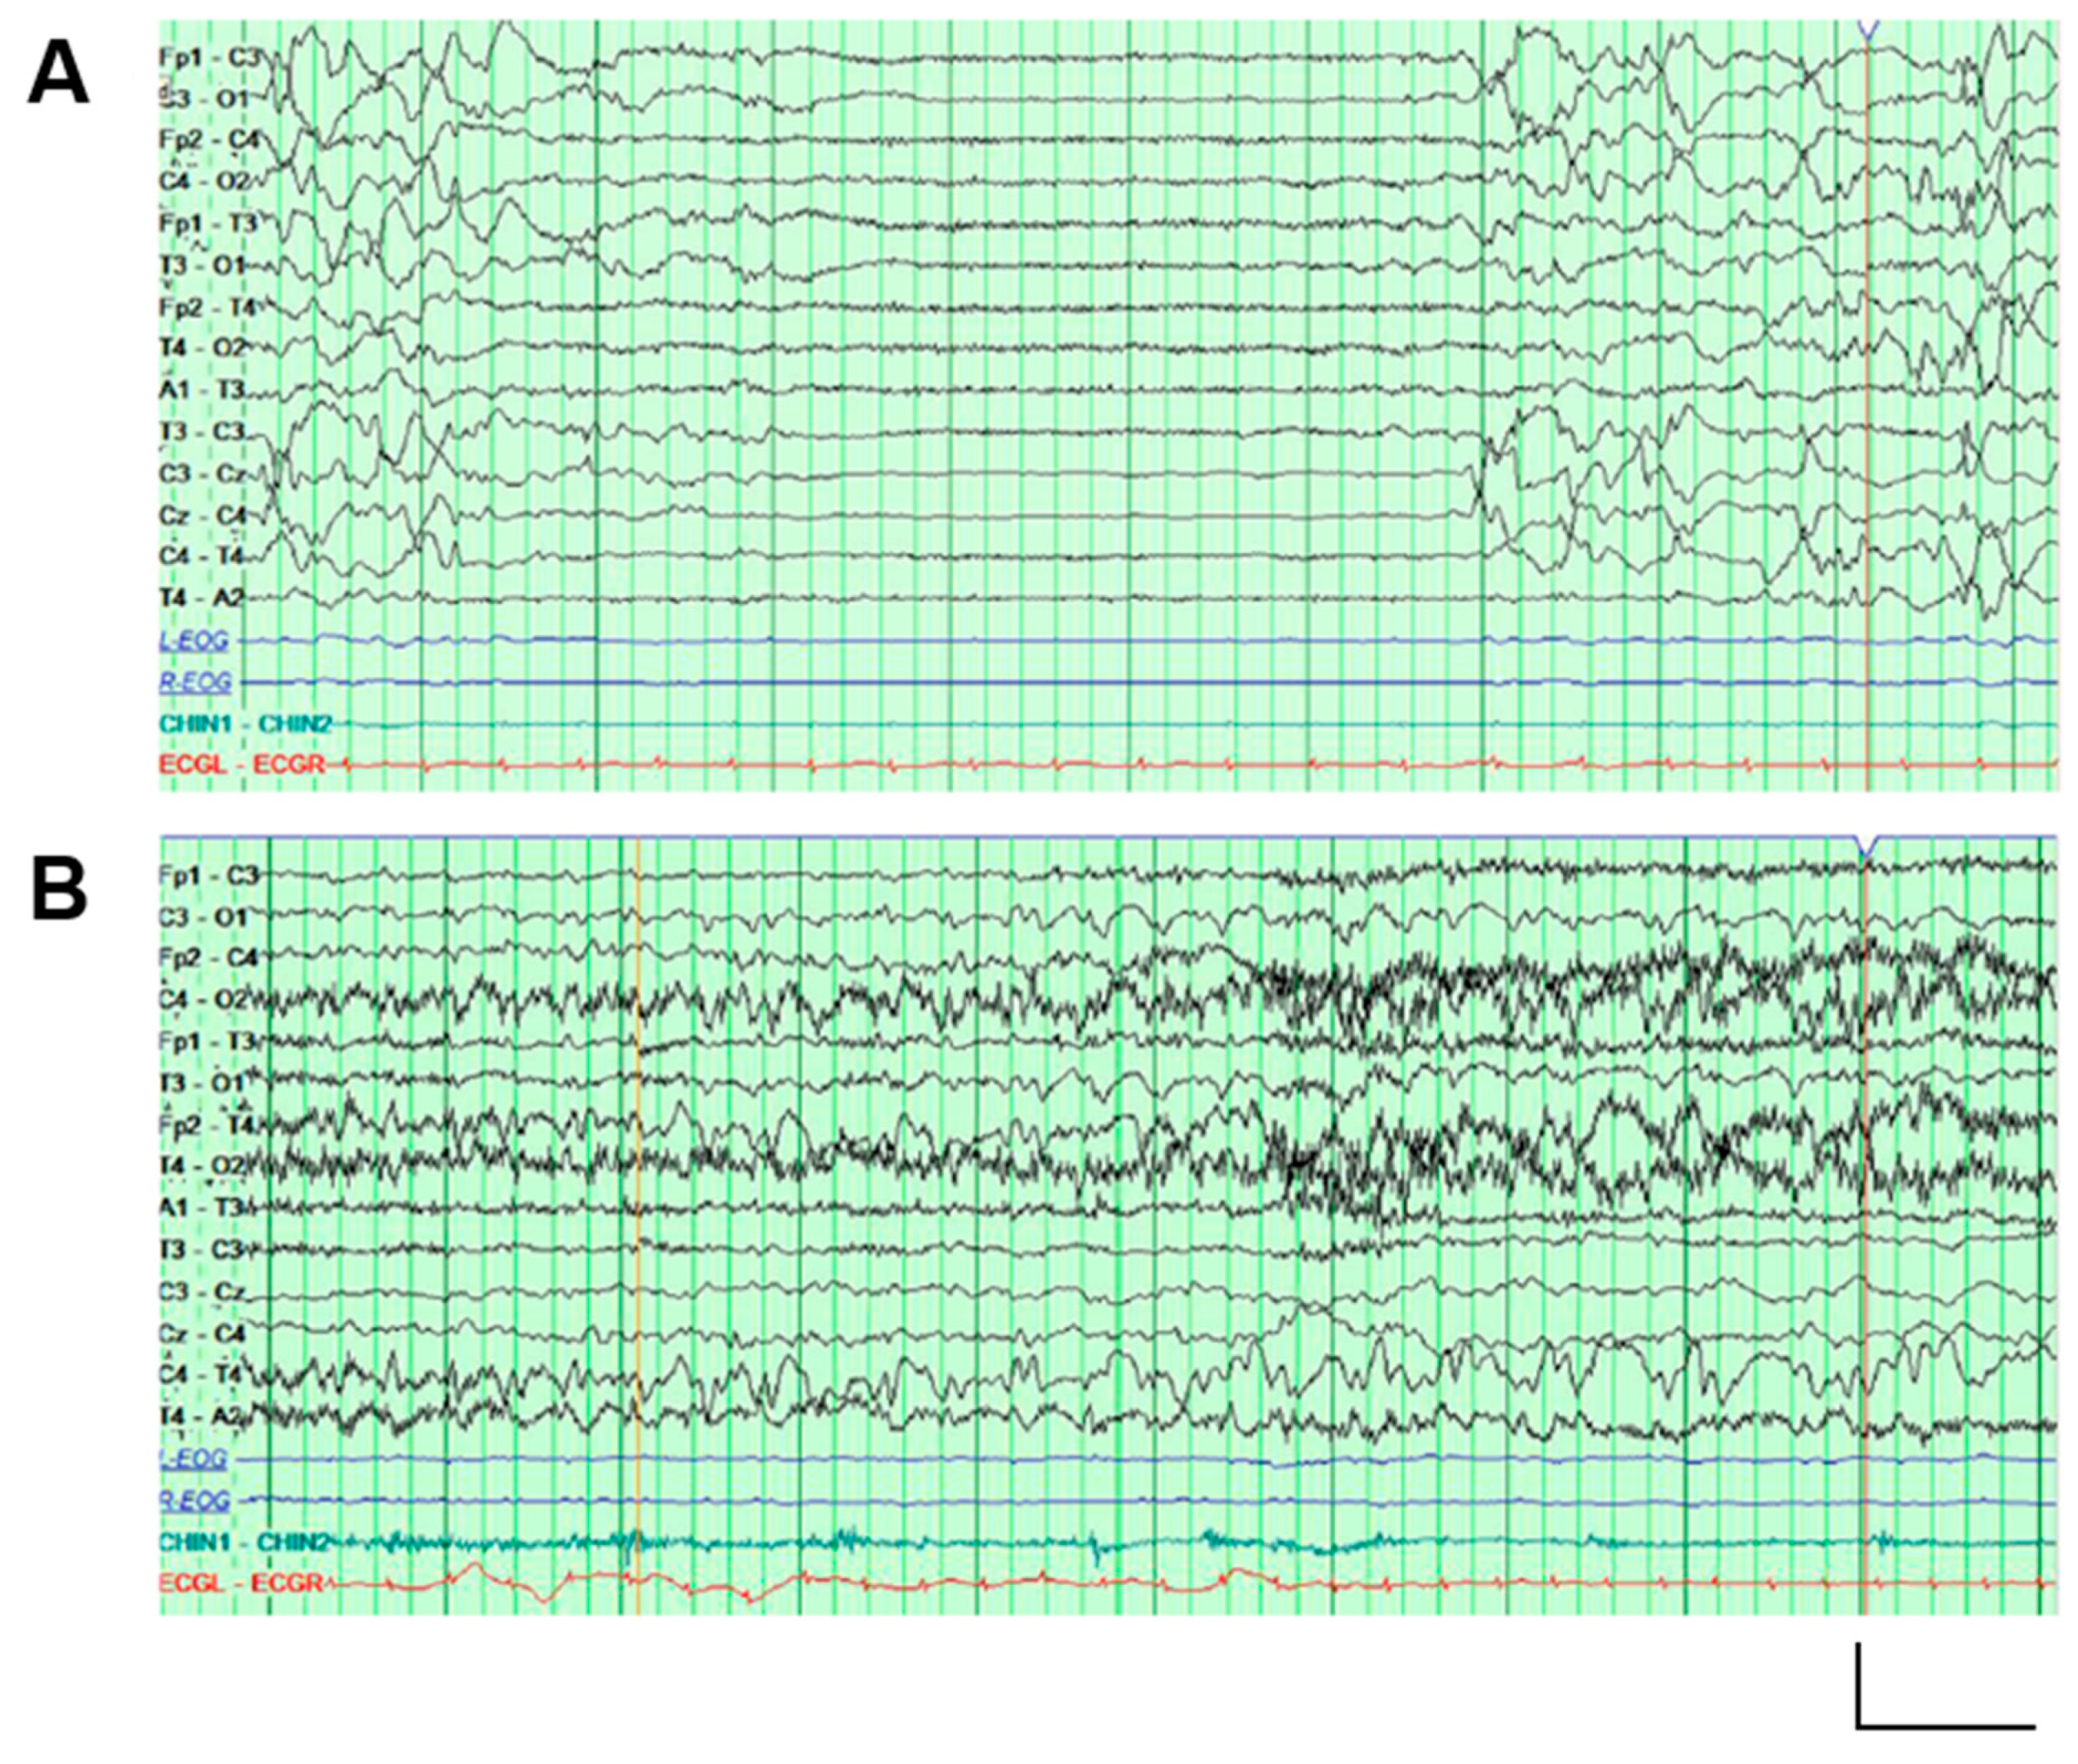

2.1. Genetic and Clinical Description of the Proband